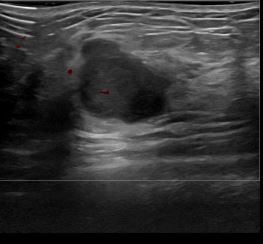

상기환자는 우측 유방 만져지는 멍우리로 내원하신 30대후반 여성분으로 의심스러운 우측혹 조직검사 시행해 유방암으로 진단되었습니다